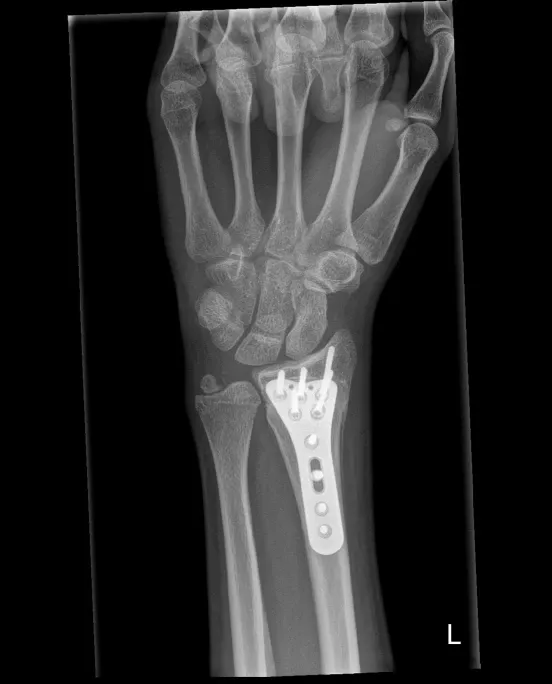

Polsfractuur

Wat is het?

Een polsfractuur is een breuk van het uiteinde van de onderarmbeenderen, meestal van de radius, soms gecombineerd met een breuk van de ulna. De breuk ontstaat meestal door een val. Breuken kunnen:

- buiten het gewricht verlopen

- in het gewricht, vaak bij een zwaarder trauma (meervoudige stukjes, verbrijzeling)

Operatief

Indien de breuk verplaatst is of onvoldoende stabiel:

- Pinnen (Kapandji-techniek): metalen pinnetjes door de huid, blijven 6 weken; risico op lichte inzakking

- Plaat en schroeven: meest gebruikte techniek; geeft meer stabiliteit en kortere gipsperiode; plaatje hoeft meestal niet verwijderd te worden

- Externe fixator: uitwendig frame, gebruikt bij open breuken

Alle ingrepen gebeuren via het chirurgisch dagziekenhuis, meestal onder plexusverdoving.